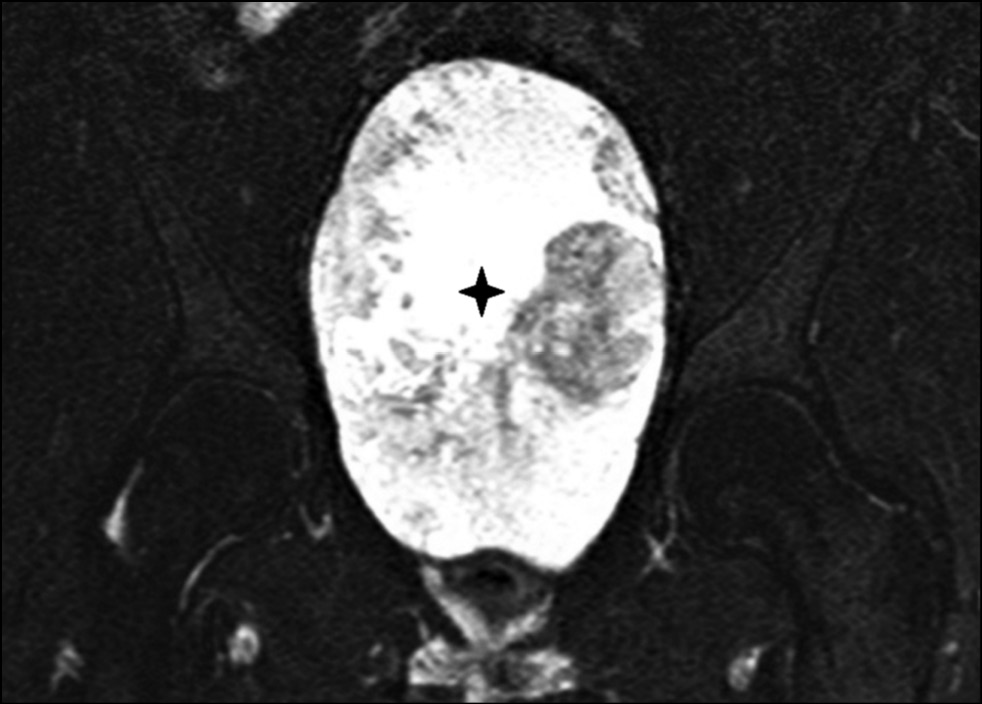

Computed tomography (CT) of the pelvis (Fig. 3) revealed a focus of lithic destruction in the S4, S5, and coccygeal vertebrae without clear contours. The destruction extended into the surrounding soft tissues and spread to the distal part of the sacral canal up to the level of the S4 vertebrae. A massive soft tissue component of the tumor, measuring up to 200 mm in length, was visualized on the anterior surface of the sacrum, reaching the level of the L5 vertebra. The tumor had clear contours on the side of the small pelvis and abdominal cavity, and it compressed and displaced the bladder and rectum. CT of the chest revealed no focal or infiltrative changes in the lungs.

Fig. 3. CT in the sagittal plane, there is a lytic focus of destruction of the C4, C5 and coccygeal vertebrae (arrow), a massive soft tissue component in the pelvic cavity, reaching the level of the L5 vertebra (asterisk).